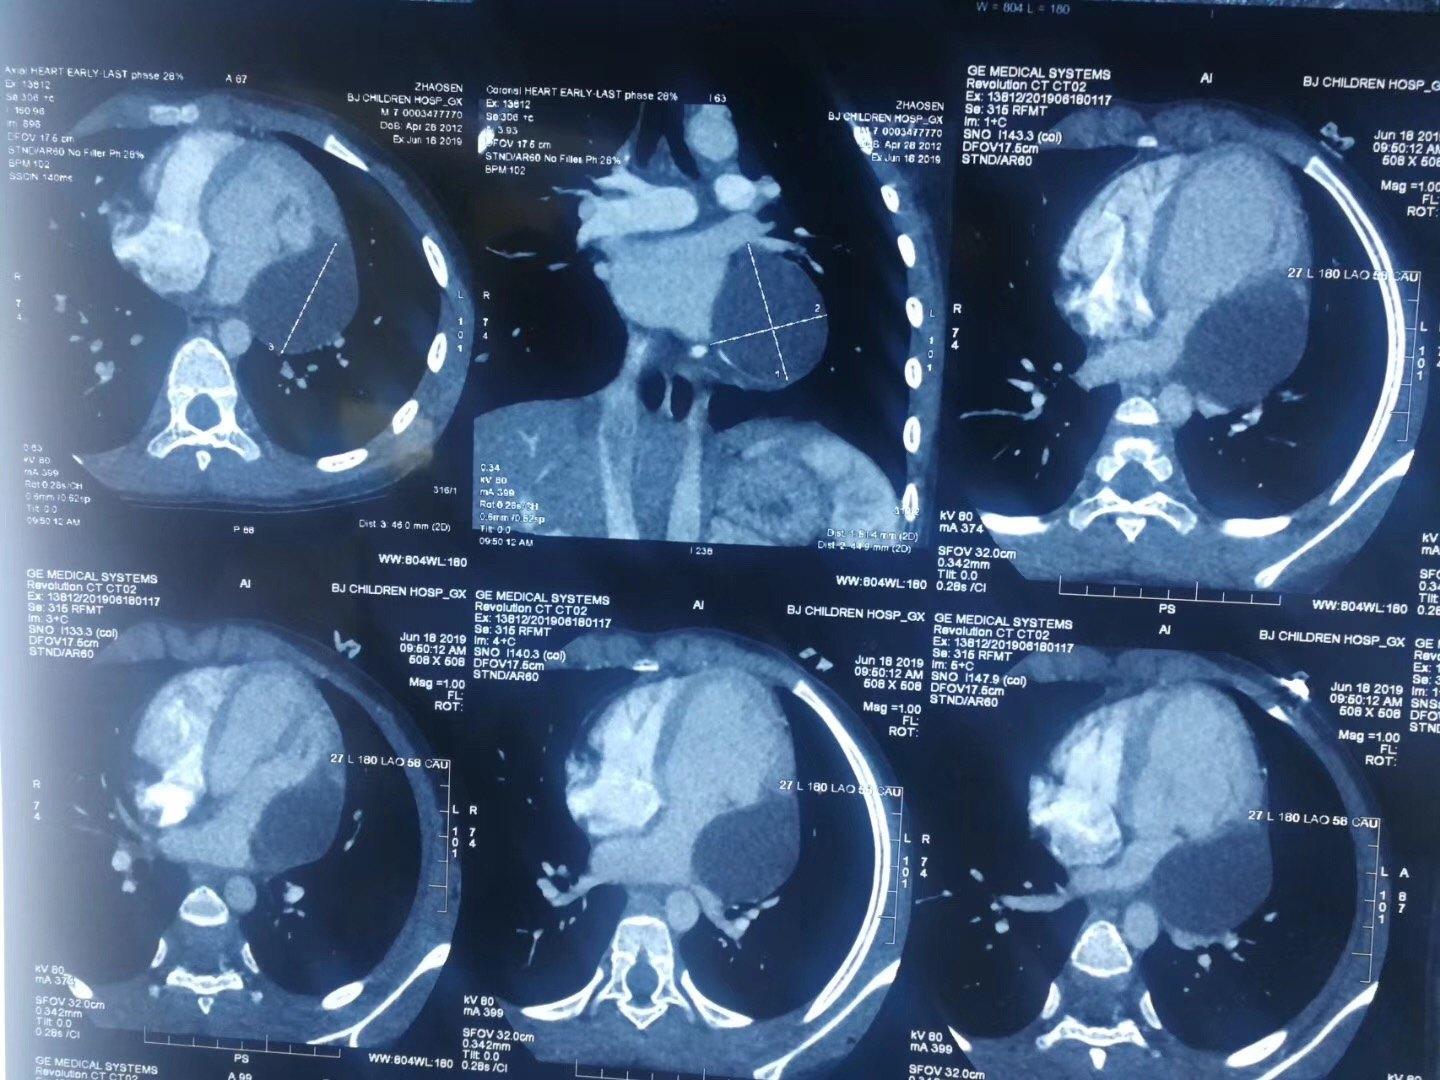

心包囊肿手术

心脏超声详细检查后确定患者为心包囊肿,住心脏大血管外科行手术治疗